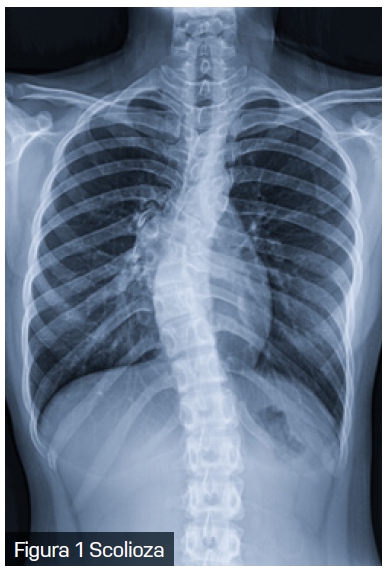

Scolioza, o deformare tridimensională a coloanei vertebrale, este o afecțiune care nu afectează doar aspectul fizic al pacientului, ci poate avea implicații semnificative și asupra sănătății respiratorii. Scolioza are o prevalență variabilă între 0,3% și 15,3% în populația generală.

Scolioza congenitală este prezentă la naștere și rezultă din malformații vertebrale sau costale, adesea asociate cu tulburări sistemice. Pe de altă parte, scolioza idiopatică, care constituie aproximativ 85% din cazuri, nu are o cauză specifică identificată și apare în perioadele de creștere rapidă. Scolioza asociată cu sindroame cunoscute este adesea subclasificată drept „scolioză sindromică”.

În fazele incipiente, scolioza este adesea asimptomatică și nu cauzează disconfort. Totuși, pe măsură ce coloana vertebrală suferă modificări în poziție și unghi, în funcție de localizarea curburii și de vârsta la care apar aceste schimbări, afecțiunea poate deveni evidentă prin simptome semnificative, inclusiv afectarea funcției respiratorii.

Modificările structurale cauzate de scolioză au un impact direct asupra mecanicii respiratorii. Deformarea coloanei vertebrale și a toracelui reduce complianța peretelui toracic, limitează mobilitatea coastelor și afectează forța musculaturii intercostale. Aceste schimbări conduc la o scădere a volumului pulmonar și determină compresia focală a căilor respiratorii. În special la copiii cu scolioză cu debut precoce, limitarea creșterii normale a toracelui și a plămânilor poate avea consecințe pe termen lung asupra dezvoltării respiratorii.

În practica clinică, pacienții cu scolioză pot dezvolta un tipar de respirație rapidă și superficială, în încercarea de a compensa rigiditatea peretelui toracic. Această adaptare conduce la o scădere a capacității de efort și la apariția dispneei de efort, una dintre primele manifestări clinice ale scoliozei. Implicarea coloanei toracice (singură sau în combinație cu segmentul lombar) în scolioză este responsabilă pentru complicațiile respiratorii și cardiovasculare, iar distorsiunea cutiei toracice crește efortul respirator necesar.

Datorită interconexiunilor complexe dintre coloana vertebrală, stern și coaste, mișcarea și rotația vertebrelor în cazul scoliozei au un impact semnificativ asupra formei toracelui, generând o latură convexă și una concavă. Pe lângă severitatea curbei coloanei vertebrale, vârsta pacientului joacă un rol în distribuția inegală a gazelor alveolare. Reducerea capacității de a efectua efort fizic la copiii cu scolioză nu se datorează doar scăderii capacității respiratorii, ci și diminuării abilității inimii de a se adapta la cerințele metabolice crescute. De asemenea, micșorarea diametrului anteroposterior al toracelui la acești copii determină o deplasare a inimii, afectând astfel funcționarea acesteia.